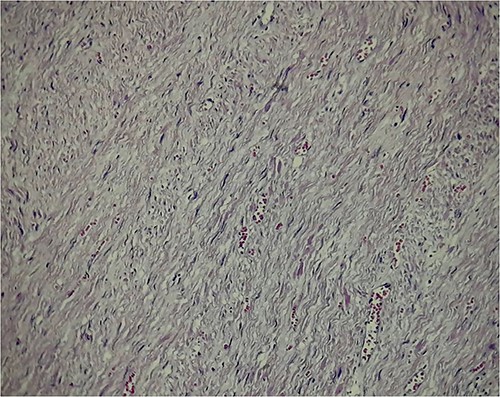

Fusiform hypercellular population in long and short bundles as well as hypercellular confluences with extensive myxoid edematous hypocellular areas.

Abundant dilated congestive vascular structures; at higher magnification of spindle cells with pale acidophilic cytoplasm, elongated nuclei of vesicular chromatin, with smooth muscular characteristics.

The histopathological study did not report any abnormal mitotic activity and the tumor was classified as an esophageal leiomyoma.